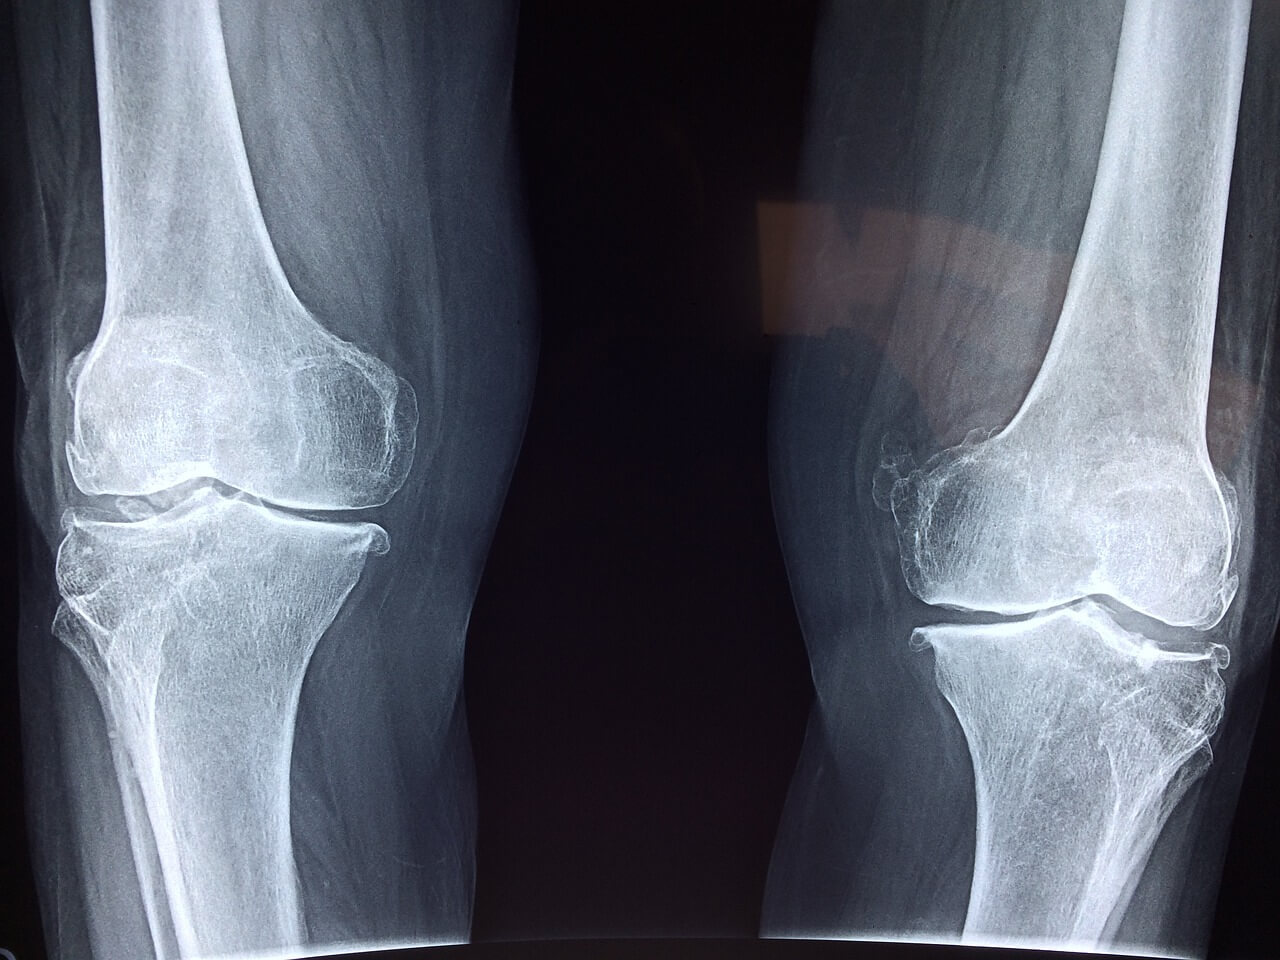

퇴행성 관절염은 관절을 보호하고 있는 연골이 퇴행하거나 점진적인 손상으로 인해 생기는 질환입니다 관절에 염증과 통증이 생기며 특발성관절염과 속발성 관절염으로 분류됩니다 특발성관절염은 일차성 관절염이라고도 불리며 특별한 기질적 원인이 없이 나이, 성별, 비만, 유전적 요소, 특정관절 부위 등의 요인에 따라 발생하며 속발성 관절염은 관절 연골에 손상을 주는 외상과 질병, 기형 등이 원인이 되어 발생합니다

퇴행성관절염의 대표적인 증상은 통증입니다 관절 부위에서 생기는 통증은 운동을 할 때 더 심해지며 통증이 심한 경우에는 뼈와 뼈가 마찰하여 마찰음이 들리기도 합니다 또한 관절 부위가 부어오르고 열이 나는 경우도 있으며 운동 제한이 생기기도 합니다 경도의 동통, 피로감, 관절의 운동장애, 종창(붓기), 관절주위의 압통, 운동 중 둔탁한 소리, 골극형성 등이 나타날 수 있습니다

| 무릎퇴행성관절염 | 초기에는 무릎 관절 부위에 통증을 느끼거나 관절을 움직일 때 약간의 불편한 마찰음 정도 나는 정도이지만 점점 진행되면서 계단을 오르내리거나 앉았다 일어나는 것들과 같은 일상적인 동작을 할 때 통증이 점점 나타나고 심해집니다 |

퇴행성관절염의 치료법은 증상의 정도에 따라 다릅니다 뼈 마디마디에 발생할 수 있으며 발생부위가 다 다르기 때문에 통증이 있는 곳의 정밀검사를 시행합니다 경증의 경우에는 약물치료와 물리치료를 통해 치료할 수 있으며 중증의 경우에는 수술이 필요할 수도 있습니다 약물치료의 경우 통증을 완화시키는 진통제와 염증을 억제하는 항염제를 복용합니다 물리치료의 경우 관절 운동법과 근력강화 운동을 통해 관절의 가동범위를 확대시키고 근육을 강화시킵니다